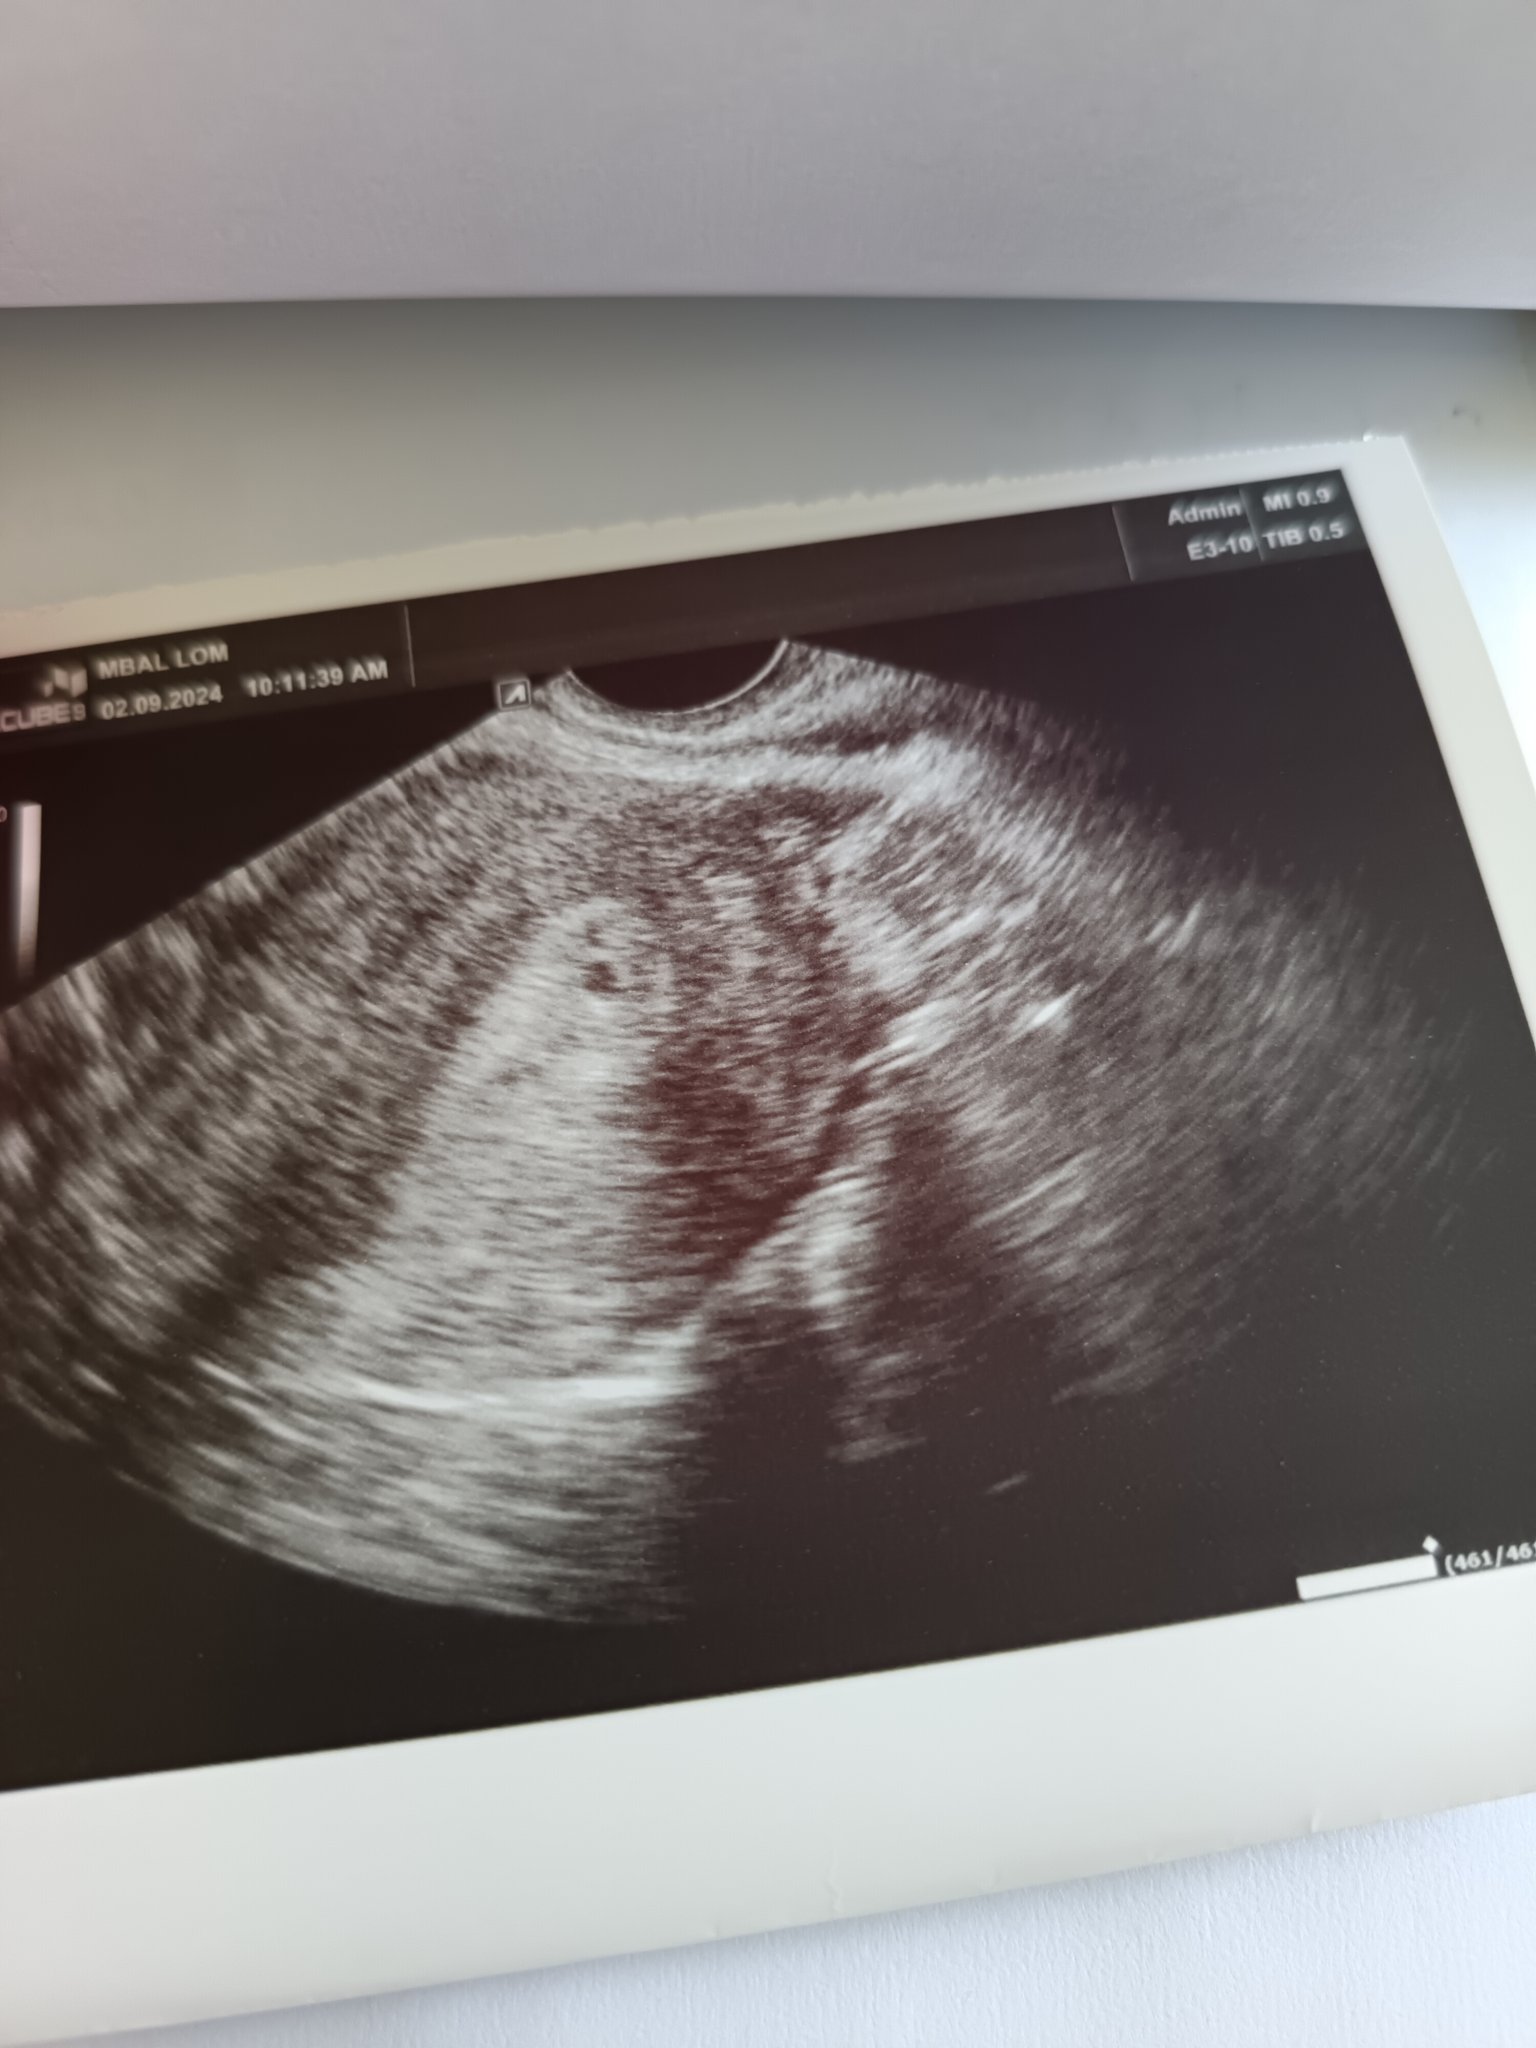

Здравейте, момичета 🤗❤️ Днес бях на преглед и бебчето е добре, има добър пулс, обаче се притесних, че отговаря на 7+1, а аз реално съм 7+3 пълни и днес ще станат 7+4. Гледаха ме през корема и мисля, че и това има значение. Предния път си отговаряше на 6+3, колкото и си бях, но прегледът беше вагинален. След две седмици отново съм на преглед. 🤗

Кактусче, не се шашкай. Аз миналата седмица в сряда бях на преглед на вагинален ехограф и докторът ми каза, че отговаря на 4 седмица, а аз трябваше да съм 5 +6. После каза, че пък отговаряло. Вчера бях на преглед, защото имах болки в кръста силни и ми се стори, че има еднократно розово зацапване. Съответно в спешното  измериха бобчето 6+2, 5 мм. По приложение трябва да е 6+3. Питах лекарката откъде е това разминаване и тя каза от ехографа и задкормилното устройство. Можеха си представиш с това отклонение почти се бях отписала... Ама бобчето е упорито.

Разликата вагинален и коремен ехограф е голяма, а и тази лекарка много спокойно ми обясни, че в началото е трудно да се определи с точност дали има изоставяне или не, защото е мн малко.

Здравейте. Преди седмица бях на преглед. Едвам се видя бременност и то с вагинален ехограф. Днес вече трябва да съм 6 седмица и 2 дни видя се вече по голяма точица, но не като за 6 гестационна седмица. АГ каза да отида след 10 дни отново за да видим как се развива и дали изобщо се развива. Хора това ще са най дългите 10 дни в живота ми. Цикълът ми е редовен на 28 дни, последна менструация на 20 юли. Това е втора бременност и е желана. По календар съм с термин края на април, но имам усещането че за съжаление няма да се получат нещата. Има ли някои минал през това?

Viliana, а пускала ли си кръвен тест на хормона ЧХГ, ако се покачва и удвоява правилно, може би нямаш повод за притеснение. Също е важно, дали техниката при твоя гинеколог е добра, може да пробваш в някоя клиника по репродуктивна медицина, там техниката е доста по - добра.

Вили, виж поста ми отгоре. И на мен ни казаха, че не се вижда добре и не отговаря на седмиците, а имах много добро ЧХГ и прогестерон. На спешен кабинет ме провериха и се отказа, че има разлика само с 1 ден от приложението.  Смени специалиста и късмет Simple Smile

Аз също препоръчвам да се пусне ЧХГ през 48 часа и преглед при друг лекар.